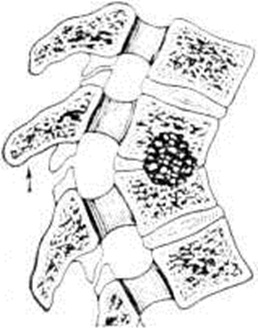

Деструкция тел позвонков сопровождается их клиновидной деформацией — это ведёт к углообразному кифотическому искривлению позвоночника (смотри полный свод знаний: Кифоз) в виде горба (gibbus), что является самым характерным признаком Спондилит У детей кифоз появляется раньше и прогрессирует быстрее, чем у взрослых. Наибольшей степени кифотическая деформация достигает при локализации процесса в грудном отделе позвоночника. С появлением кифоза постепенно деформируется вся грудная клетка, смещаются и сдавливаются находящиеся в ней сосуды и органы, развивается легочно-сердечная недостаточность и другие нарушения. При боковой деструкции тел позвонков развивается сколиотическая деформация (смотри полный свод знаний: Сколиоз), более характерная для поясничного отдела позвоночника (рисунок 3). Чаще имеют место сочетанные деформации. Межпозвоночные диски вследствие нарушения трофики постепенно уменьшаются в размерах и истончаются. Тела позвонков, разрушаясь, сближаются, соприкасаются и при длительно существующем процессе образуют нередко единый конгломерат, блок тел позвонков, включающий очаги деструкции, остатки разволокнённых дисков. Задние отделы позвоночника также сливаются воедино в виде панциря, закрывающего спинной мозг.

Искривление позвоночника при Спондилит в виде углообразной кифотической деформации обусловлено разрушением тел позвонков, их компрессионным переломом и клиновидной деформацией. При компрессии одного — двух тел позвонков остистый отросток поднимается кверху и выпячивается, образуя «точечный» горб (рисунок 4). При распространении процесса кифотическая деформация увеличивается. В шейном и поясничном отделах горб обычно невелик или отсутствует полностью, и деформация позвоночника чаще проявляется сглаженностью лордоза (смотри полный свод знаний). При патологический процессе в грудном, а особенно в поясничном отделе позвоночника туловище больного укорачивается, вследствие чего возникает диспропорция между туловищем и конечностями. По мере затихания процесса прогрессирование деформации замедляется, а затем прекращается. Одновременно улучшается общее состояние больных. В стадии затихания боли обычно отсутствуют, хотя может оставаться болезненность позвоночника, обусловленная его деформацией, нарушением опороспособности, патологический подвижностью, компрессией корешков спинномозговых нервов.